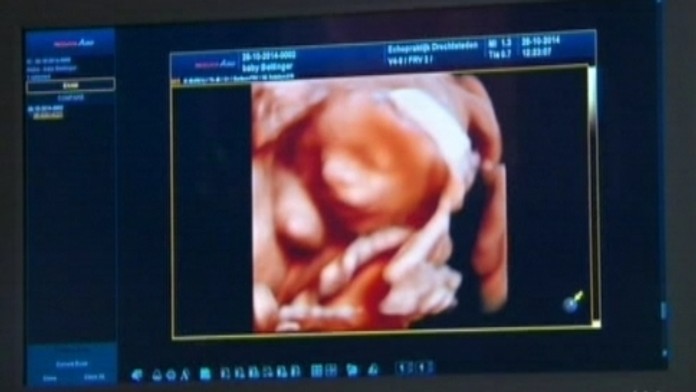

Snímku z ultrazvuku im lekár vytlačí na 3D tlačiarni. Za takýto model nenarodeného dieťatka platia v Holandsku budúci rodičia 600 eur.

Tehotné ženy si po novom môžu vziať do náručia svoje nenarodené dieťa. Snímku z ultrazvuku im lekár vytlačí na 3D tlačiarni. Nápad sa niektorým pozdáva, iným sa zdá byť zvrátený.

Anneke si najskôr svoje dieťatko pozrie na monitore ultrazvuku. Vo chvíli, keď ho vidieť najlepšie, lekárka dá snímku tlačiť. Potom už stačí len čakať, kým si 3D tlačiareň urobí svoju prácu. Za takýto model nenarodeného dieťatka platia v Holandsku budúci rodičia 600 eur.